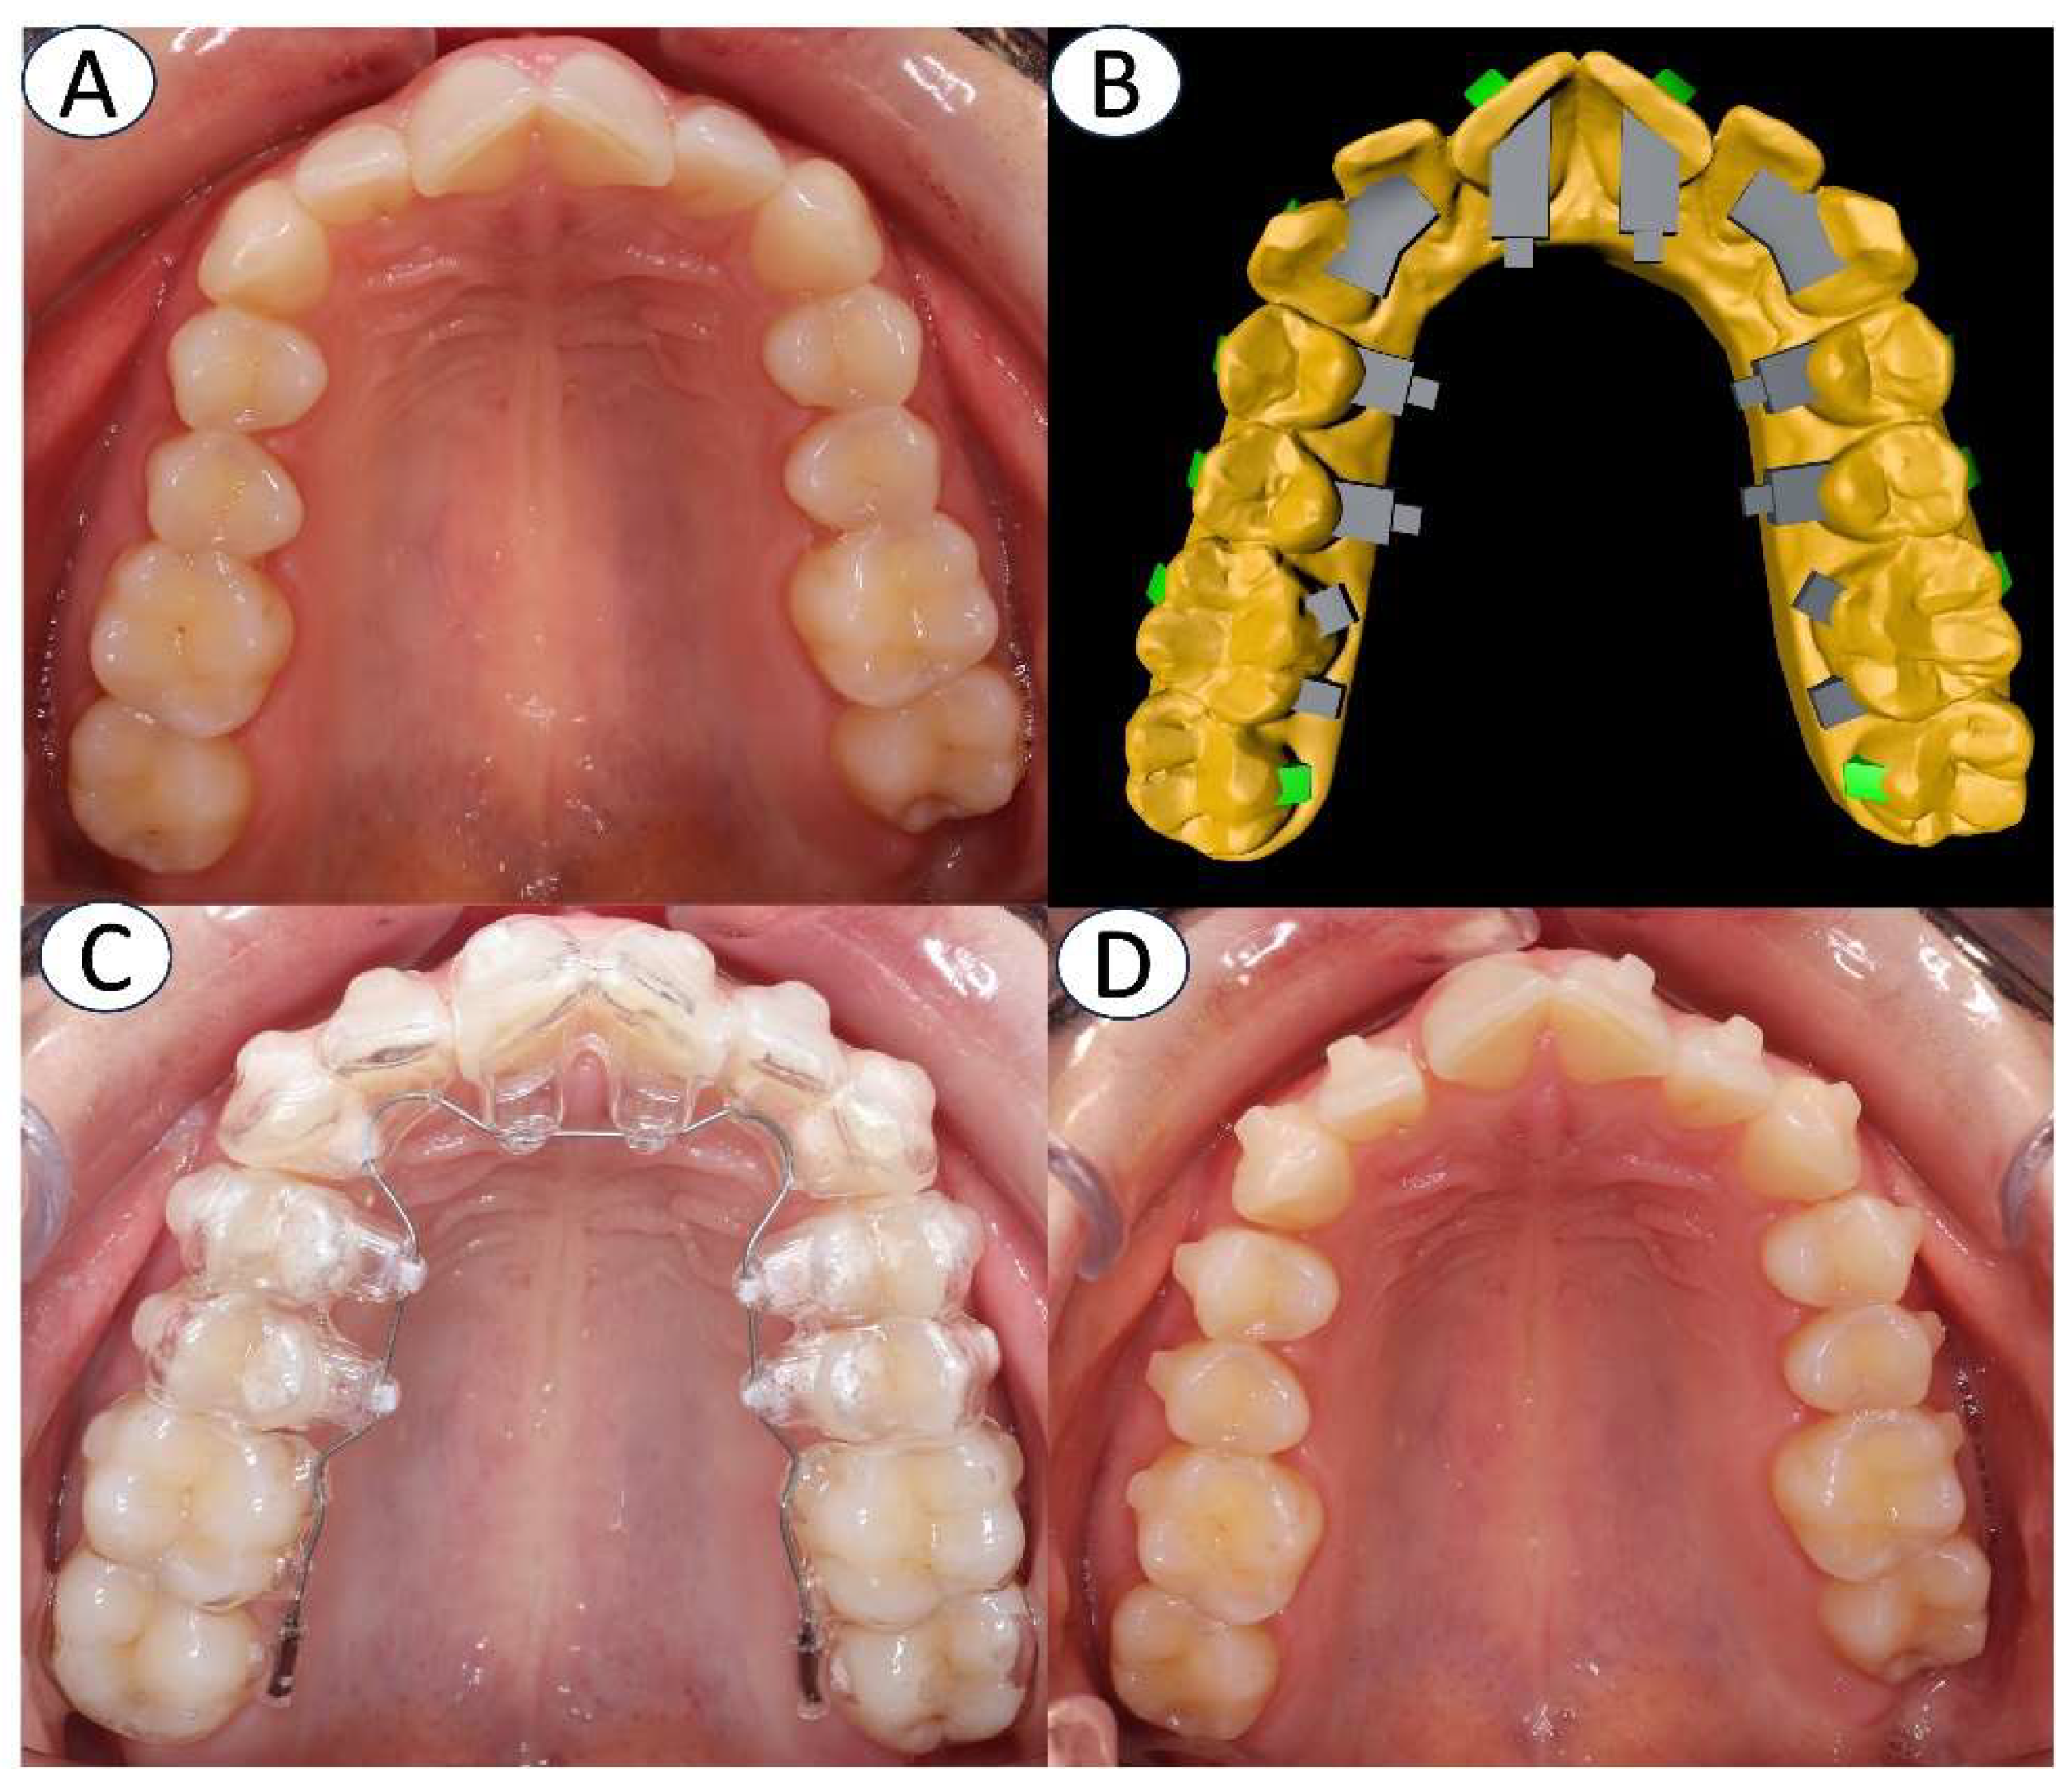

Figure 2. Hybrid aligner in subject of GT group. A: picture previous to treatment. B: digital treatment design. C: First day of hybrid aligner in mouth. D: picture after 2 months of treatment.